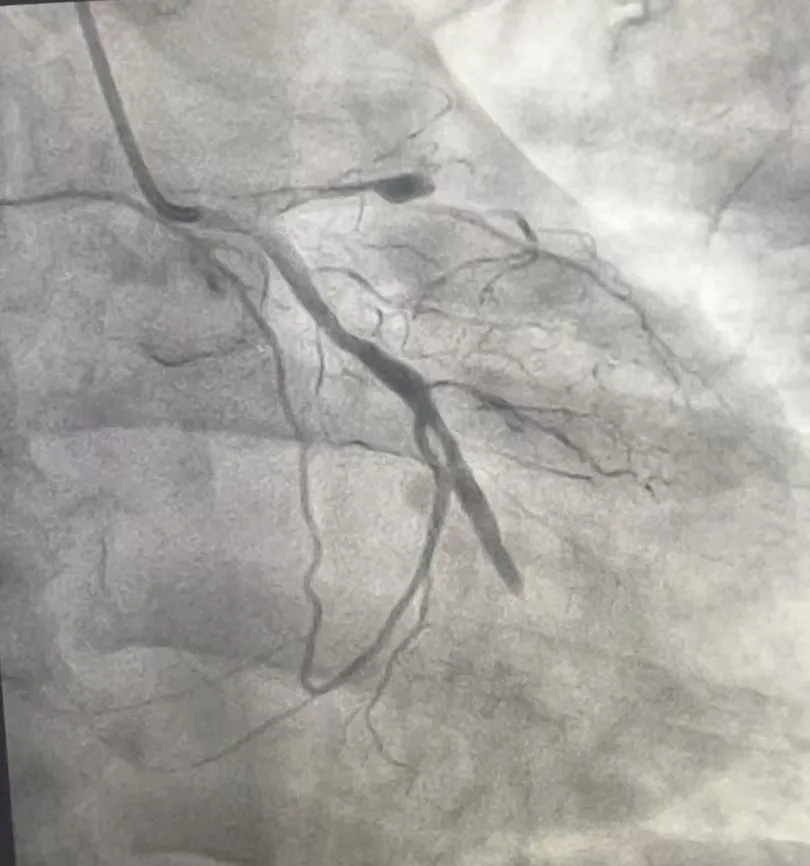

造影揭秘:三支血管“堵”成“危机四伏”

心脏血管造影检查提示,张先生的三支主要血管均存在严重病变。

• 前降支近段完全闭塞,该血管心脏供血的“主干道”之一,负责左心室前壁血液供应,堵塞后极易引发大面积心梗;

• 回旋支中远段完全闭塞,供应心脏侧壁血液,闭塞会加重心肌缺血范围;

• 右冠状动脉中远段弥漫性狭窄,最重处达70%-80%,虽未完全堵死,但狭窄严重,随时可能进展为急性闭塞。

(术前影像)

患者前降支和回旋支同时完全堵塞,相当于心脏的两条重要“高速公路”彻底中断,仅靠右冠残余血流勉强维持,随时可能猝死。